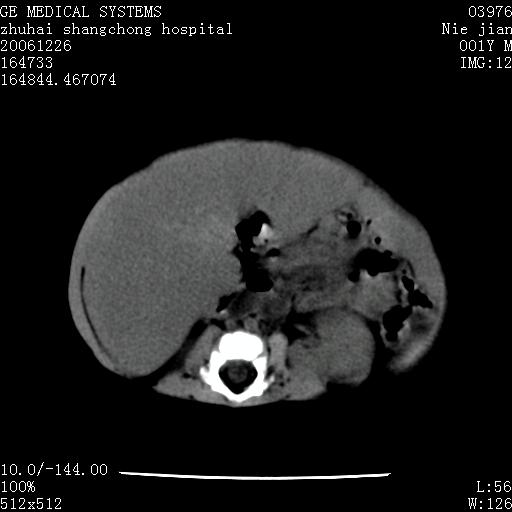

3个月婴儿腹胀来看。

【影像特征】

1、肝明显增大,肝弥漫性低密度灶。

2、肾上腺区见类圆形肿块,其内密度不均,见片状偏高密度。

【诊断】

1、肝弥漫性病变,考虑急性肝炎致广泛脂肪浸润可能性大。

2、肾上腺区占位,假性肿瘤?肾上腺血肿(感染所致)?

1、关键着眼点:肝脏弥漫性病变内有没有走形的血管,仔细看部分低密度内有血管影(要有增强扫描作为证据就好了),说明并非肿瘤样病变,而是脂肪浸润。即可能不是转移瘤或原发肿瘤,低密度的形态上看,是片状,也不像肿瘤。

2、儿童肝炎最常见的是感染,有时食入性损害或药物也可致肝脏炎症,肝炎致大空泡型脂肪变性,是一种无痛性疾病,无症状,病因有营养异常、代谢性疾病、药物及病毒感染。所以脂肪变性与感染有关。

3、肝炎的结局是肝硬化,而恰恰一年后复查,已有肝硬化表现。肿瘤一般那会消失,那叫奇迹。

4、肾上腺出血也可见于败血症及感染,通常包块在数周内消失,ct表现包块内有偏高密度,可能是亚急性血肿的表现。假性肿瘤即腹部肠管积液、扩张血管及邻近结构的伪像。自然会消失。

5、因此,感染可以贯穿一切,解释一切。肿瘤自然消退?可能吗?那些应要无道理的创造奇迹的事情会那么容易发生吗?